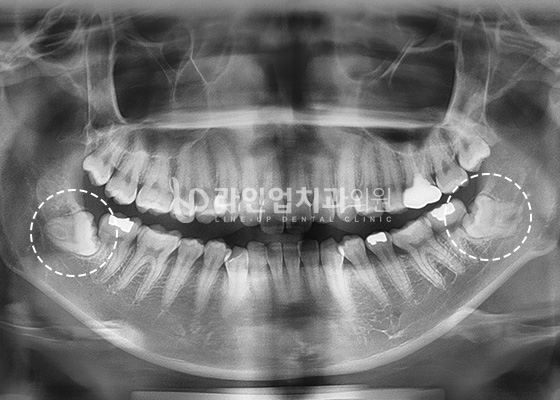

ПРИМЕРЫ УДАЛЕНИЯ ЗУБА МУДРОСТИ

Before

After